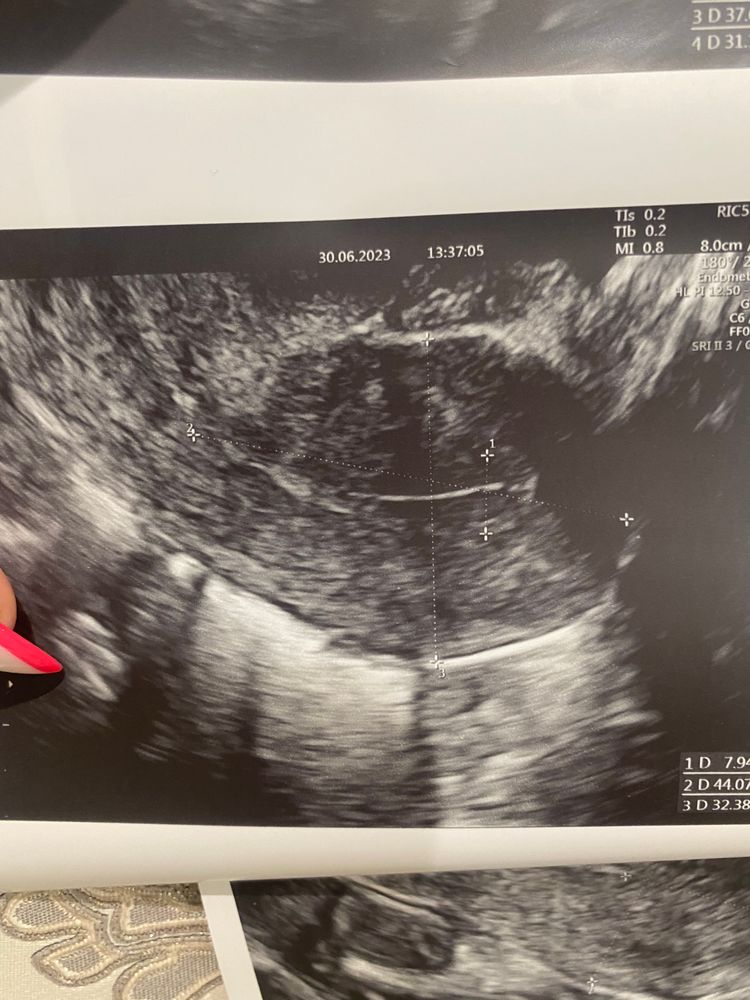

Девочки , подскажите пожалуйста кто разбирается в узи

Да нет никаких кист, это доминантный фолликул. Размер 19х17. Нормальный преовуляторный фолик. У меня таких фоток тьма, желтое тело вообще по другому выглядит

Виктория, думаю просто когда неочевидно они только предполагают. Сказано фоллик должен быть идеально круглый - значит если не круглый, то ЖТ) почему киста только не поняла, размер то нормальный)

Это не жёлтое тело. Это дф. Отслеживали овуляцию по УЗИ несколько месяцев и жёлтое тело оно конечно совсем другое.

По-моему у вас фолликулярная киста, судя по узи яичника и по эндометрию

Девочки че то с мамой поговорила и за переживала климакс в 36 лет у неё тип начался( УЗИ после бхб. Киста, эндометриоз?